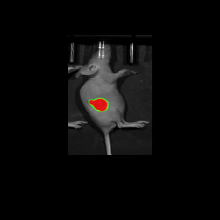

광학이미징

실시간으로 생체 내부의 동적 변화를 관찰 할 수 있어, 약물이 체내에 어떻게 분포되고 작용하는지 확인 할 수 있습니다. 또한, 약물이 표적 조직에 얼마나 효과적으로 작용하는지를 시각화하여 확인 할 수 있습니다. 동일한 동물에서 반복 측정이 가능하여 데이터의 일관성과 재현성을 높일 수 있습니다.